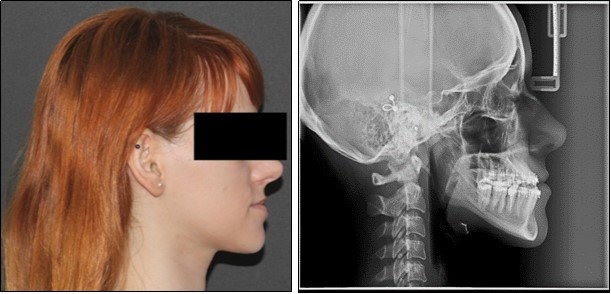

Orthodontic examination digital photographs were taken before the patient underwent the initial cinical examination. Frontal esthetic analysis revealed a long face, an increased third floor of the face and an asymmetry due to mandibular deviation to the left. Lateral view analysis disclosed a concave profile, with a deficient nasomaxillary area and proeminent chin. The lower lip was protruded, the upper lip was retruded and the mentolabial anlge was reduced. (Figure 1)

Figure 1.Initial extraoral photographs

Initial extraoral photographs

The panoramic radiograph examination showed impacted bilateral mandibular third molars, and one maxillary third molar.Cephalometric analysis disclosed a skeletal class III (ANB -5 degrees), with a retruded maxilla and a protruded mandible (SNA 78 degrees and SNB 83 degrees). The patient is a hyperdivergent type, with FMA 30 degrees and IMPA 77 degrees, which suggests retruded lower incisors. Examination of soft tissue on the profile radiograph shows a concave profile and a protruded lower lip. (Figure 3).

Figure 3.Initial panoramic and lateral cephalometric radiographs

Initial panoramic and  lateral cephalometric radiographs